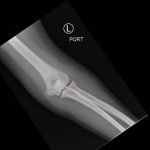

Elbow dislocations are classified by the position of the radio-ulnar joint relative to the humerus.1 Images 1, 2, and 3 show a left posterior elbow dislocation; the radius and ulna are displaced posteriorly with respect to the distal humerus. The lateral view of the elbow most clearly shows this: trochlear notch of the ulna is empty and displaced posteriorly relative to the trochlea. There is no associated fracture. Images 4 and 5 show the elbow status-post reduction, demonstrating proper alignment of the distal humerus with the radius and ulna.